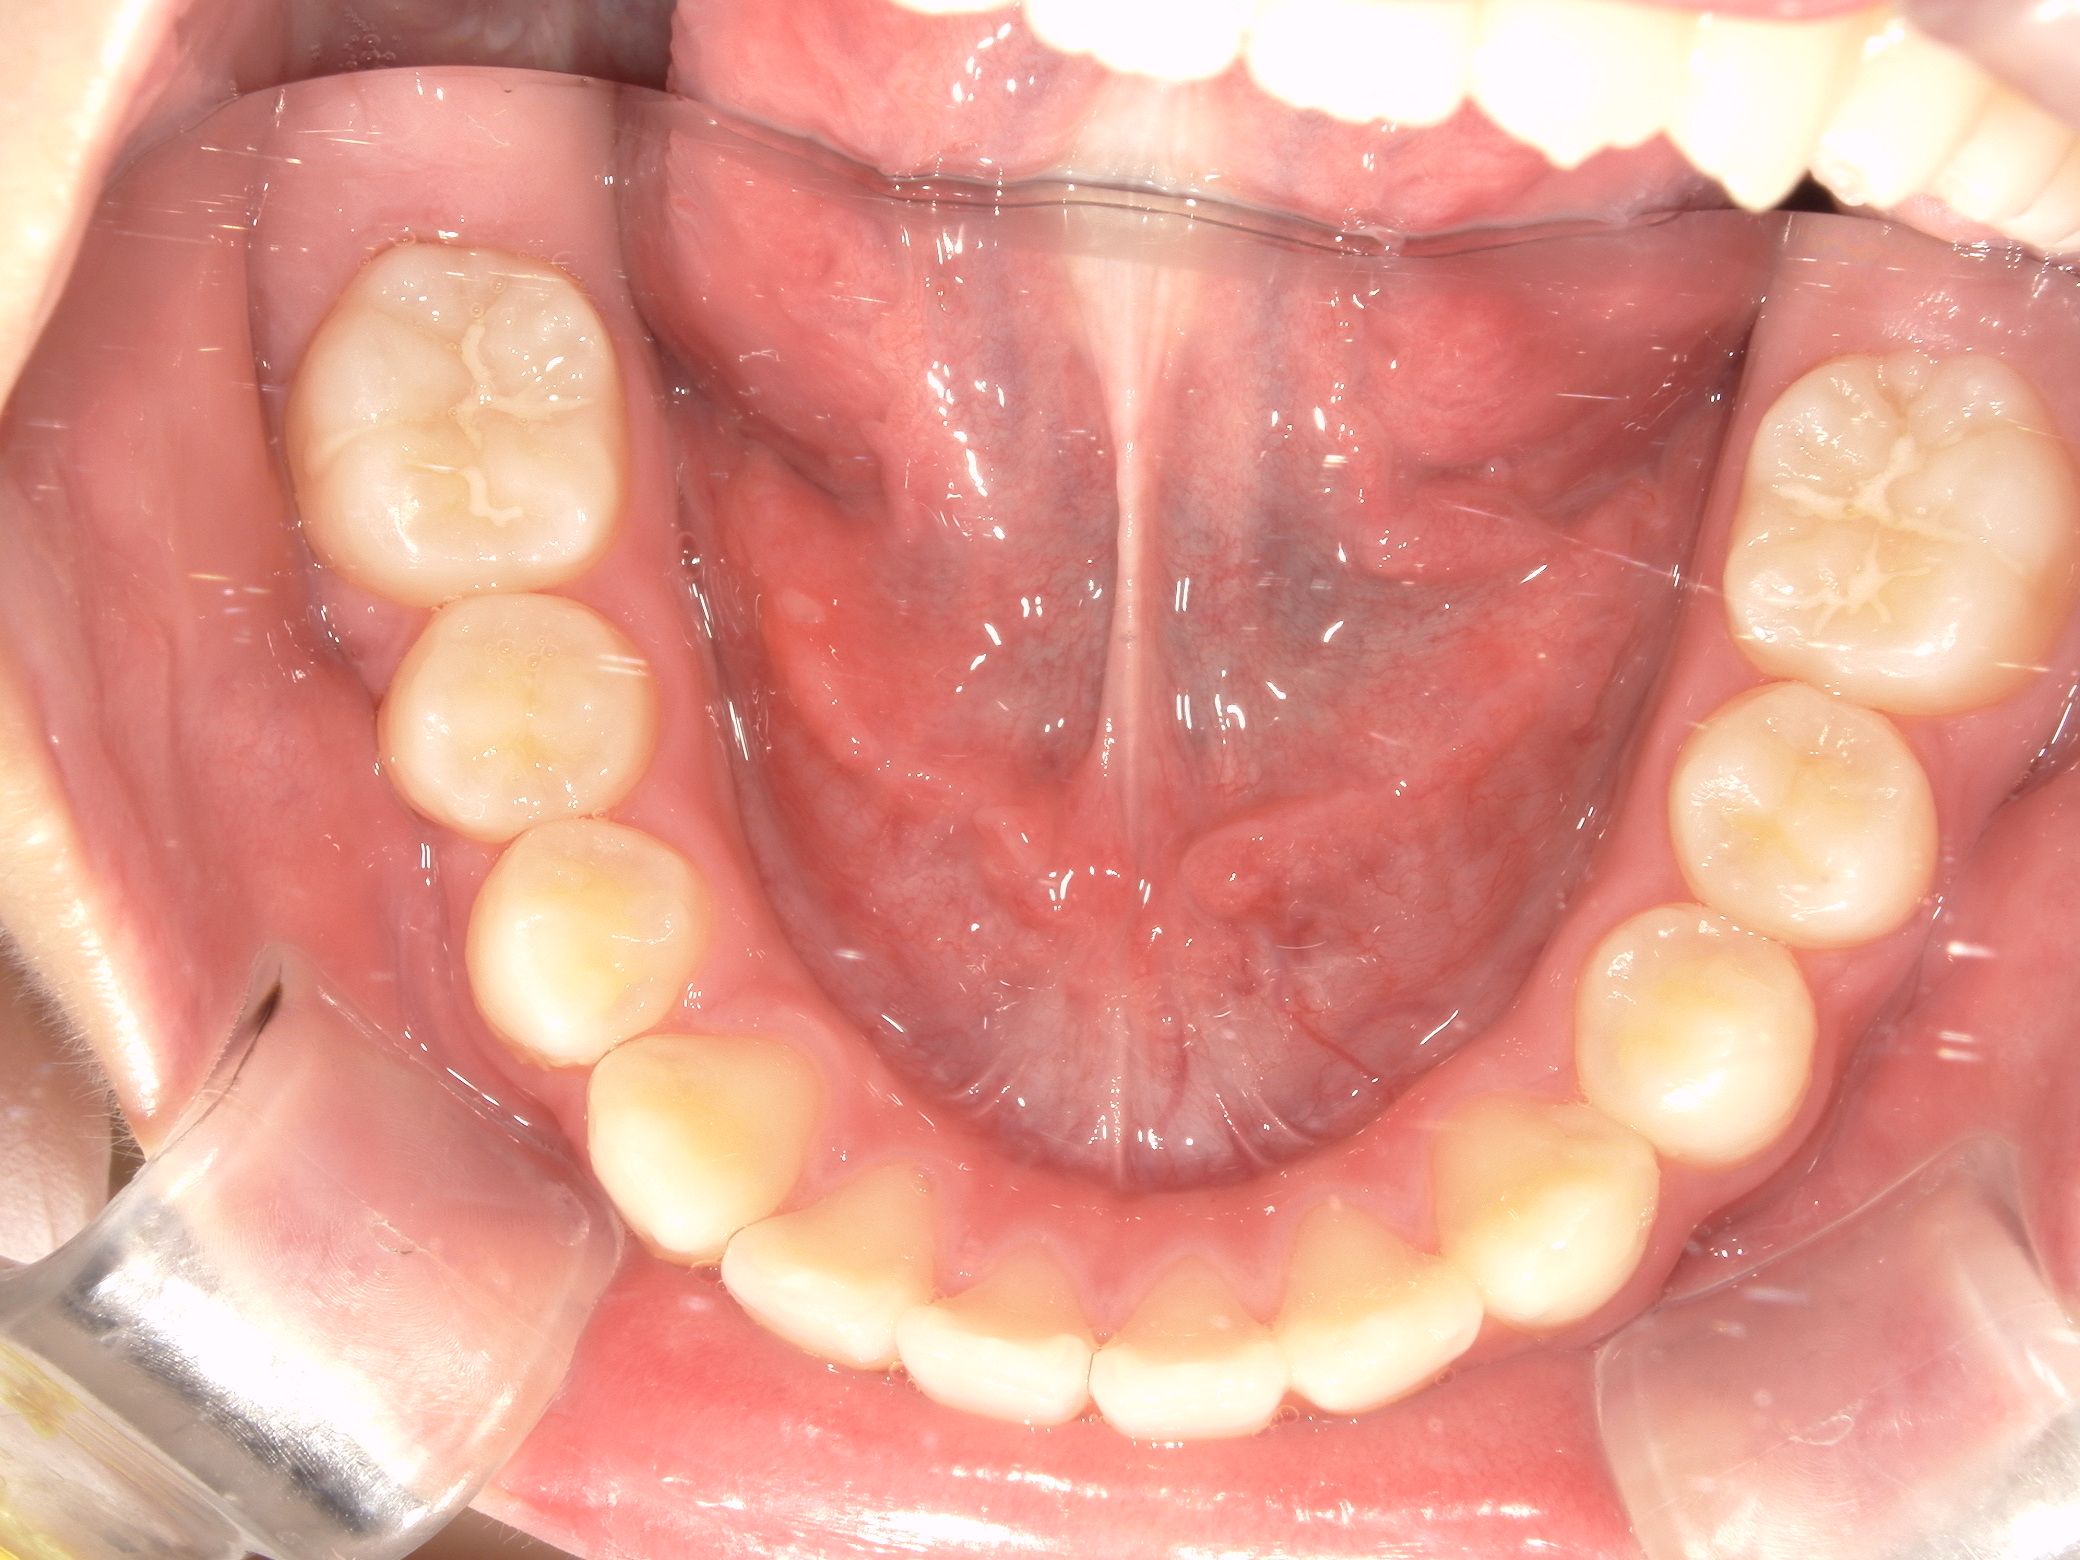

治療前 Before

上の歯並びがガタついています